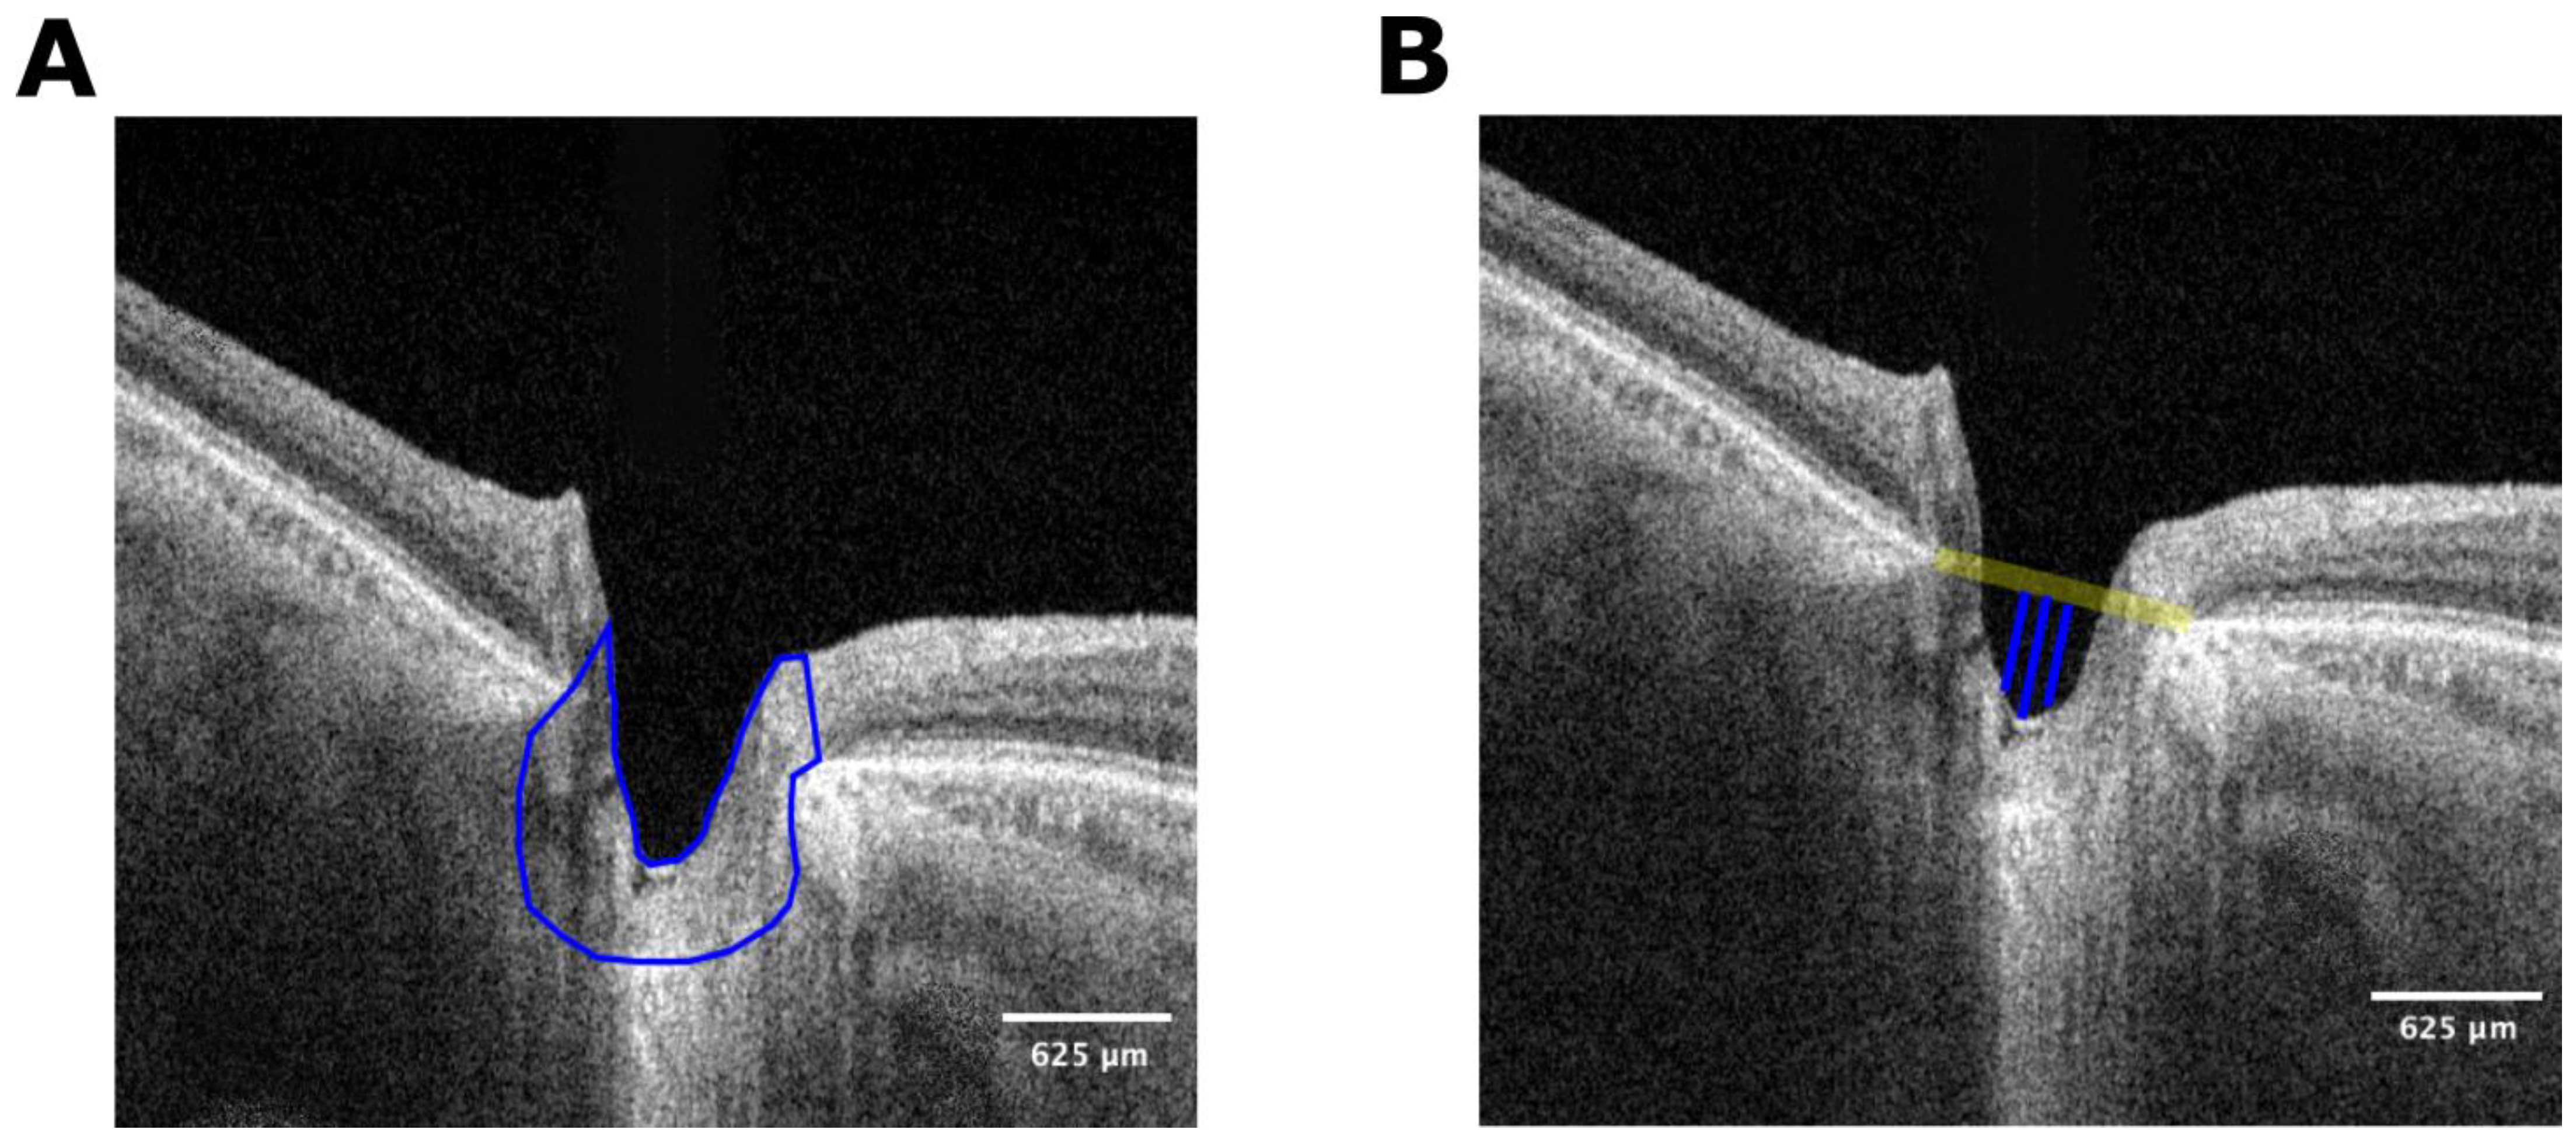

2.2. Image Processing

- Solano, M.M.; Richer, E.; Cheriet, F.; Lesk, M.R.; Costantino, S. Mapping Pulsatile Optic Nerve Head Deformation Using OCT. Ophthalmol. Sci. 2022, 2, 100205. [Google Scholar] [CrossRef]